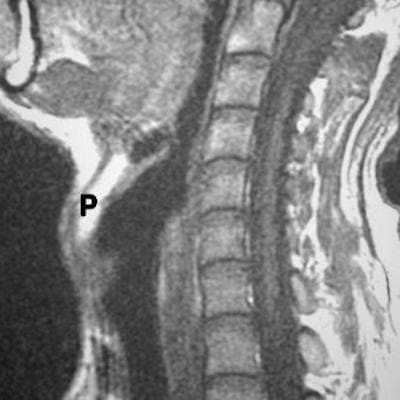

(Слева) При аксиальной КТ с КУ визуализируется крупная опухоль (ПКР), заполняющая около гортанное пространство с обеих сторон, пересекающая среднюю линию и прорастающая в черпалонадгортанные складки Обратите внимание, что опухоль вызывает сужение просвета дыхательных путей; оцените также вторичное опухолевое поражение лимфоузла III уровня справа.

(Справа) При МРТ Т1ВИ в сагиттальной проекции визуализируется массивная опухоль (ПКР) преддверия гортани, заполняющая предгортанное пространство и замещающая жировую ткань, но не затрагивающая часть надгортанника выше подъязычной кости. КТ с КУ или МРТ в сагиттальной плоскости отчетливо демонстрируют инвазию предгортанной жировой ткани, что означает как минимум стадию Т3.2. КТ при плоскоклеточном раке преддверия гортани: